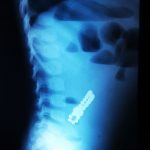

Dr. Adriana Constantineanu, medic specialist în chirurgie pediatrică atrage atenția asupra pericolului din spatele jucăriilor cu magnet. Acestea îi pot distra pe copii și pot fi fascinați de multitudinea de culori vii care îi duce cu gândul pe cei mici la bomboane, înghițindu-le.

Acești magneți sunt foarte puternici, iar ingestia lor poate duce la probleme gastrointestinale grave. Odată înghițiți sunt atrași unul spre altul chiar dacă se găsesc în secțiuni diferite ale tubului digestiv. O ansă intestinală prinsă între acești magneți se poate perfora ducând la tratament chirurgical de urgență. În secția noastră, de la începutul anului s-au prezentat trei cazuri, două fete și un băiat, cu vârste cuprinse între 2 și 4 ani. Aceștia au suferit perforații la nivelul intestinului subțire și au necesitat intervenții pentru îndepartarea porțiunii de intestin afectate”, a precizat dr. Adriana Constantineanu.